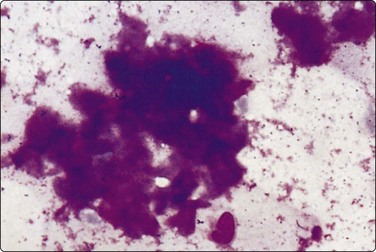

Fig. 4.4 Amyloid tumor

Clumps of amorphous acellular purple material (MGG, HP).

Solitary deposits of amyloid, so-called amyloid tumors, are occasionally found submucosally in the hypopharynx, the larynx and other parts of the upper respiratory tract. Amyloid stains an intense magenta color with MGG, less specific yellowish-green with Papanicolaou. It has a fairly dense amorphous texture with a finely fibrillar rather than hyaline structure discernible in high power. In FNB smears, the amyloid may be associated with histiocytic giant cells, lymphocytes or epithelial and/or mesenchymal cells from surrounding tissues (see also Chapter 14).

Problems and differential diagnosis

The appearances of amyloid in cytological smears are not always characteristic enough to be diagnostic. It can be confused with dense thyroid colloid or hyalinised fibrous stroma.39 Its nature should therefore be confirmed by staining with Congo red and polarisation. In the head and neck, the possibility of origin from medullary thyroid carcinoma, primary or metastatic, must always be considered, and immunostaining for calcitonin performed.